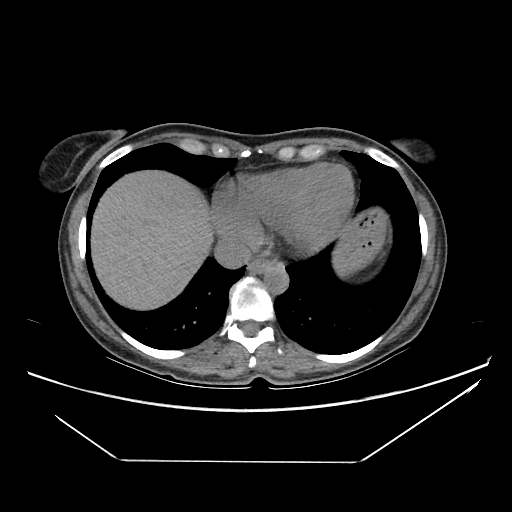

Generated VENOUS CT scan (A→B translation)

Full window (WL 1023.5, WW 4095 β†’ Low βˆ’1024, High +3071)

Lung window (WL -600, WW 1500 β†’ Low βˆ’1350, High +150)

Mediastinum window (WL 40, WW 400 β†’ Low βˆ’160, High +240)